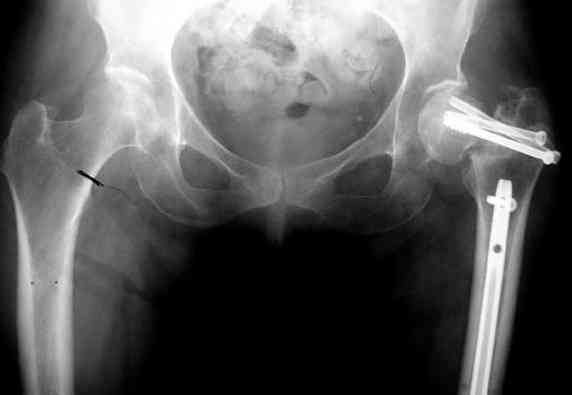

На снимках ложный сустав шейки бедра, несостоятельность фиксации. По положению шурупа можно предсказать ложный сустав, например, если screw backup за кортикальный слой около 15-20 мм, и также изменение угла от первоначального.

№2-3 типичная ошибка несоблюдения концепции параллельности шурупов, нарушение-фиксация поперечным допольнительным шурупом для приближения отломка в результате не сработало метод параллельных шурупов